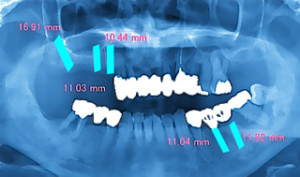

インプラント 治療計画

コラム「インプラント 治療計画」の画像